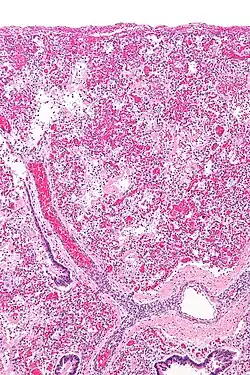

Fig 2. Diffuse Alveolar Damage (DAD)

Leukocyte-mediated pulmonary inflammation is a key pathophysiological mechanism involved in ARDS.[2] This is presumed to cause Diffuse Alveolar Damage (DAD) [Fig 2]. On histologic examination, DAD is present in 40-60% of patients clinically diagnosed as having ARDS.[3]